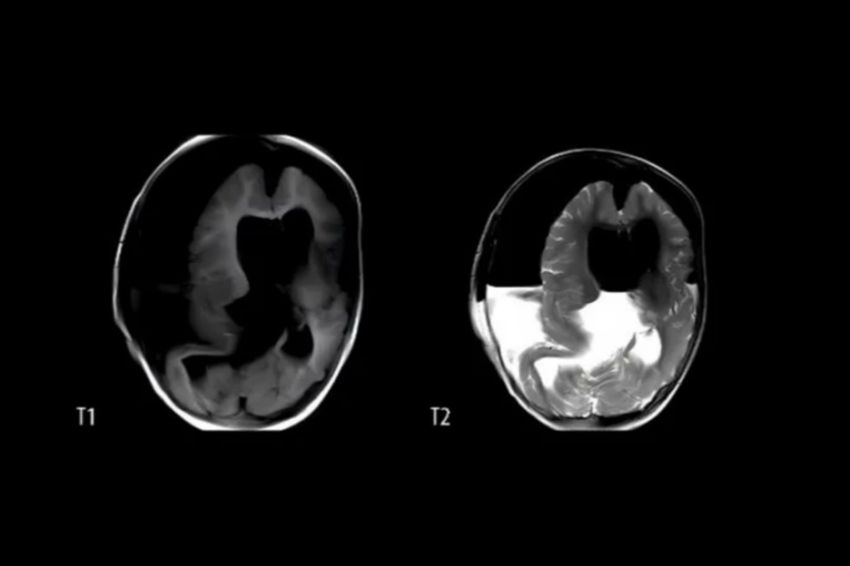

Hasil pemindaian menunjukkan bahwa kondisi anak perempuan ini disebabkan oleh janin yang terperangkap di dalam kepalanya sendiri. Janin yang terperangkap di kepala anak 1 tahun asal China itu sudah memiliki tulang belakang, organ, dan jari.